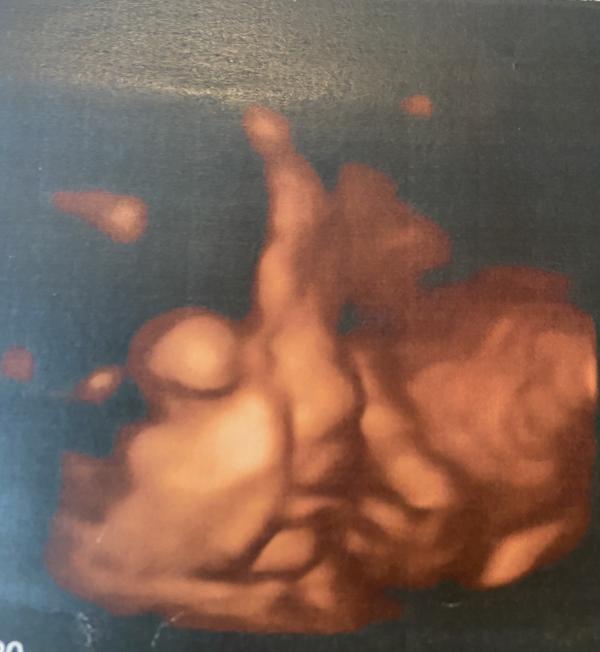

Сегодня с мужем ходили на узи😍Внепланово, чисто для себя)))Господи, сколько эмоций, сколько счастья❤️Наша малышка уже примерно 2 кг😘Наша радость, наше счастье как же мы тебя ждём❤️❤️❤️

Третий скрининг был в 5 жк, где я наблюдаюсь. Впечатлений ни каких, убитый кабинет, допотопная техника, не плохой доктор, но я мне даже ни одним глазом не дали взглянуть на малышку. А сегодня, просто решили с мужем сходить вместе на 3д узи пошли в медэксперт, остались очень довольны хороший доктор, все рассказала, все посмотрела, все показала)))